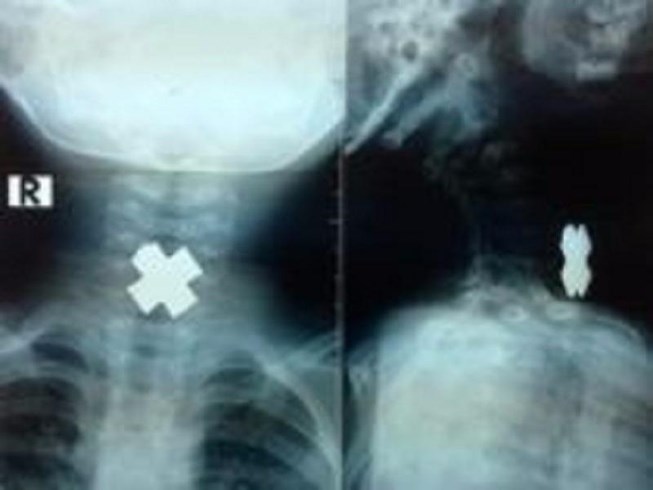

Click vào ảnh để xem 4 hình ảnh minh họa

Nội soi được thực hiện để xác định dị vật và loại bỏ sự tắc nghẽn. Nguyên nhân của tắc nghẽn cũng được xác định và điều trị có thể bao gồm: thuốc ức chế bơm Proton, giãn nở thực quản và phẫu thuật. Xạ trị, hóa trị hoặc phẫu thuật có thể được áp dụng cho các bệnh nhân ung thư.